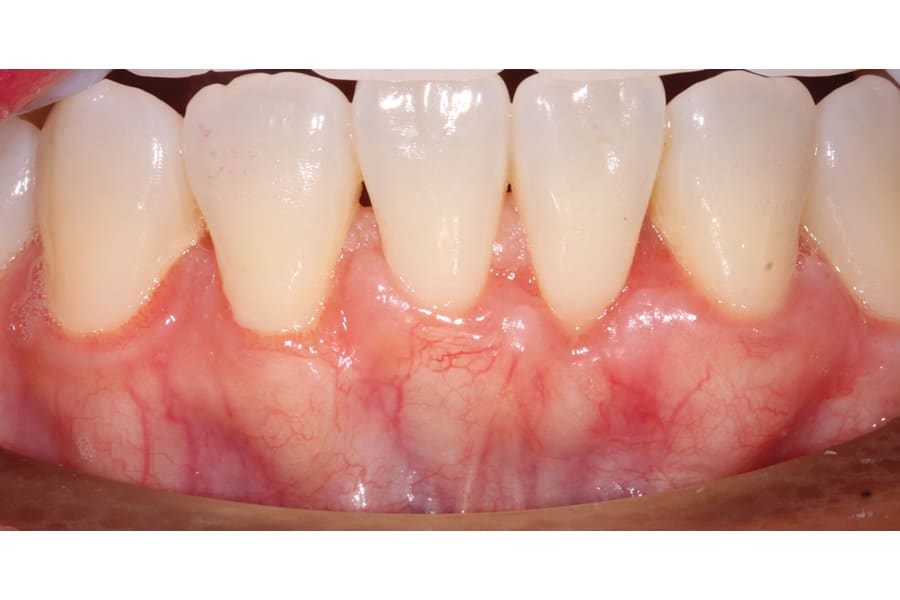

There are, however, some unfavorable long-term ramifications of this design. Due to the nature of stainless steel, which has memory and over time will partially return to its original shape, these twisted lingual retainers may "unwind" or uncoil and exert unintended forces on the teeth to which they are bonded (Figure 5 and Figure 6, Figure 8 through Figure 11, Figure 14 through Figure 16). This leads to excessive labial or lingual root torquing movements, often resulting in highly undesirable recessions, dehiscences, and fenestrations. Because it may take years for this occurrence to manifest, the orthodontist (who usually places the retainer) is typically both unaware of the situation, as he or she does not customarily follow patients for such long-term periods, and free of blame. The periodontal implications of this outcome can be highly detrimental, as seen in the cases presented herein.

Although spontaneous improvement of the investing tissues is often observed through orthodontic correction (Figure 7 and Figure 13),5 additional corrective action is frequently indicated afterwards, particularly when cosmetics are to be considered. A recession defect case is depicted in Figure 17 through Figure 26 in which corrective action was necessary and accomplished through aligner therapy followed by connective tissue grafting.6 It should be noted that although this corrective scheme may successfully achieve an acceptable cosmetic and functional result, it is not likely a regenerative outcome in the sense that a previously dehisced root surface typically will not attain ligamentous insertion into freshly laid cementum. A long junctional epithelium or connective tissue attachment at best is the more likely outcome. Consequently, a preventive approach initially would be more desirable.